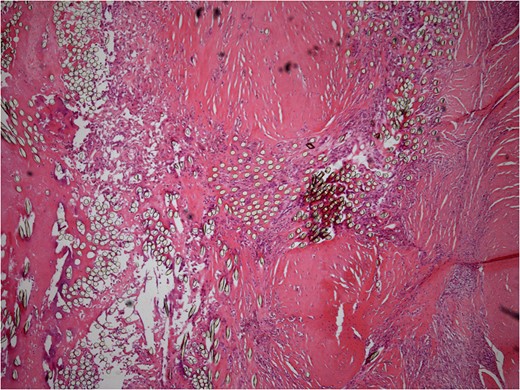

He underwent surgery to explore the tendon where an irregular, cystic, fibrofatty lesion was identified within the tendon (Figs 3–5). This was successfully resected and sent for histology which showed a florid granulomatous and histiocytic response to the suture material, in keeping with a suture granuloma (Figs 6 and 7). There was histological evidence of the abscess extending into the muscle (Fig. 8).

Low power histology slide showing foreign body giant cell reaction to suture material.

40× histology slide showing foreign body giant cell reaction to suture material.